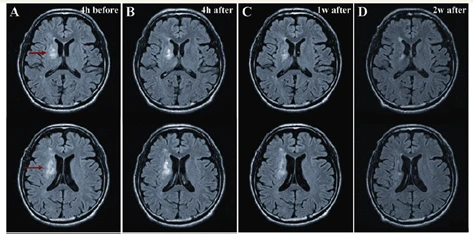

骨髄由来幹細胞での治療後にMRIにより脳の損傷部を観察した写真です。治療後、時間の経過とともに病変部(白い部分)が縮小していることがわかります。

(Honmou O et al., Brain. 2011 Jun;134(Pt 6):1790-807.)